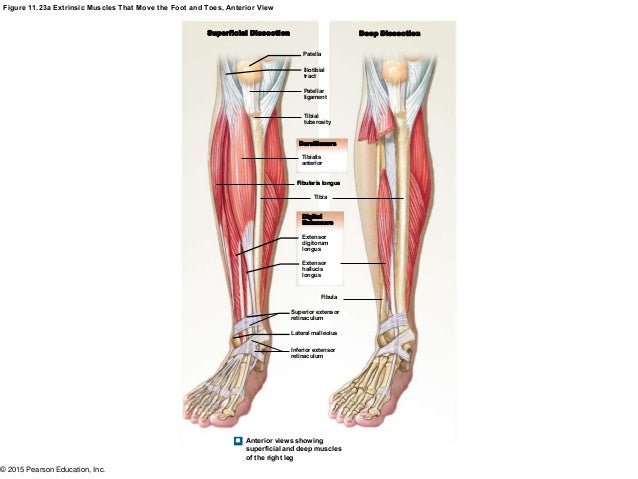

Extensor Digitorum Brevis: The extensor digitorum brevis muscle is a deep-lying intrinsic muscle lying beneath the tendon of the extensor digitorum longus.Attachments: Originates from the tibia and transitions into a tendon, passes into the foot, splits into four, and attaches to the toes.Extensor Digitorum Longus: The extensor digitorum longus is a deep-lying extrinsic muscle that lies runs down the length of the tibia.Movement of the foot and toes requires the action of many muscles.Īlthough many extrinsic muscles attach within the dorsal compartment, there are only three intrinsic muscles which act on the foot and two extrinsic muscles which act on the foot rather than the ankle.